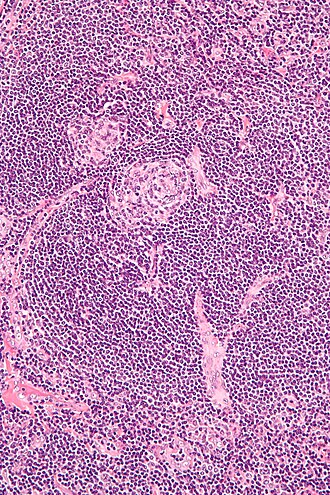

Castleman disease (hyaline-vascular variant). H&E stain.

Hyaline-vascular variant

Features:[6][7][8]

• Pale concentric (expanded) mantle zone lymphocytes - key feature.

• "Regressed follicles" - germinal center (pale area) is small.

• "Lollipops":

• Germinal centers fed by prominent (radially penetrating sclerotic) vessels; lollipop-like appearance.

• Two germinal centers in one follicle, so called "twinning".

• Hyaline material (pink acellular stuff on H&E) in germinal center.

• Sinuses effaced (lost).

• Mitoses absent.